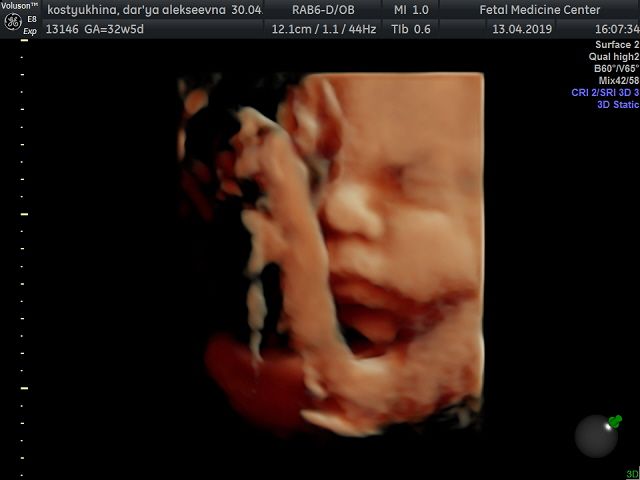

Вот и добралась до флешки))) Наш сыночек в цвете ? смотрю и не верю!!! Какое же чудо природы, да и техники фото через органы? еще 1,5 мес и состоится встреча всей жизни ? Вчера после скрининга зашли в кафе израильское, малыш ликует от этой пищи!!! С собой взяли паштет из тунца с кедровыми орешками и сушеной клюквой, села кушать и снова танцы ? блин даже от сладкого такого нет ? А что любят ваши малыши?)

Господи, честно, как мой! ?? Может они близнецы ????